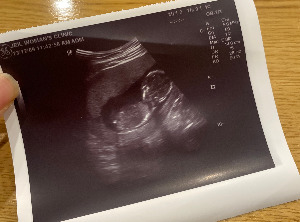

14주 차 정도가 되면 초음파를 통해 어느 정도 성별예측이 가능하다고 한다. 기존에 다니던 병원의 초음파 기계는 작은 갈비뼈까지 보일 정도로 선명하고 고퀄의 기계였으나, 동네의 작은 산부인과의원은 옛날 정사각형 모니터로 흐릿한 초음파를 보게 된다. 난 초음파를 알아볼 수 없었으나 선생님께 성별 힌트라도 얻을 수 있을까 싶어 기대가 되었다.

KakaoTalk_20231228_144658799.jpg 14주 차 김띠용

공복으로 가서 그런지, 초음파가 흐려서 그런지 아기의 움직임이 뚜렷하진 않았으나 여전히 건강한 모습이었다. 무뚝뚝한 선생님은 아기의 상태가 어떤지 제대로 설명도 안 해주시고 "별 이상 없습니다. 입덧약 2주 치 드리면 될까요"로 진료를 마치려고 했다. 나는 "아 네, 그런데 혹시 성별은 아직 모르는 거죠?"라고 물었다.